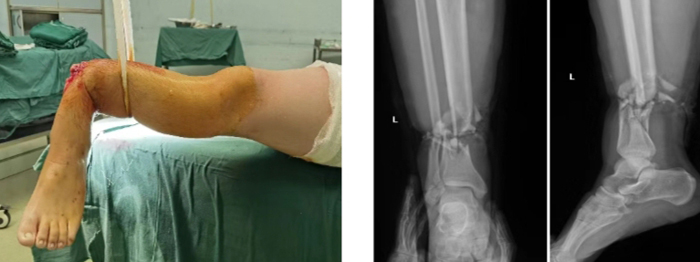

當(dāng)晚,值班醫(yī)師接到會(huì)診電話:患者趙某,男,29歲,因鋼板砸傷致左小腿離斷2小時(shí)急診入院。經(jīng)初步評(píng)估,患者傷口遠(yuǎn)端組織離斷,僅少許皮膚相連,遠(yuǎn)端肢體無(wú)血運(yùn),創(chuàng)口內(nèi)組織毀損嚴(yán)重。經(jīng)與患者及其家屬充分溝通后,開(kāi)通急診綠色通道進(jìn)入手術(shù)室。